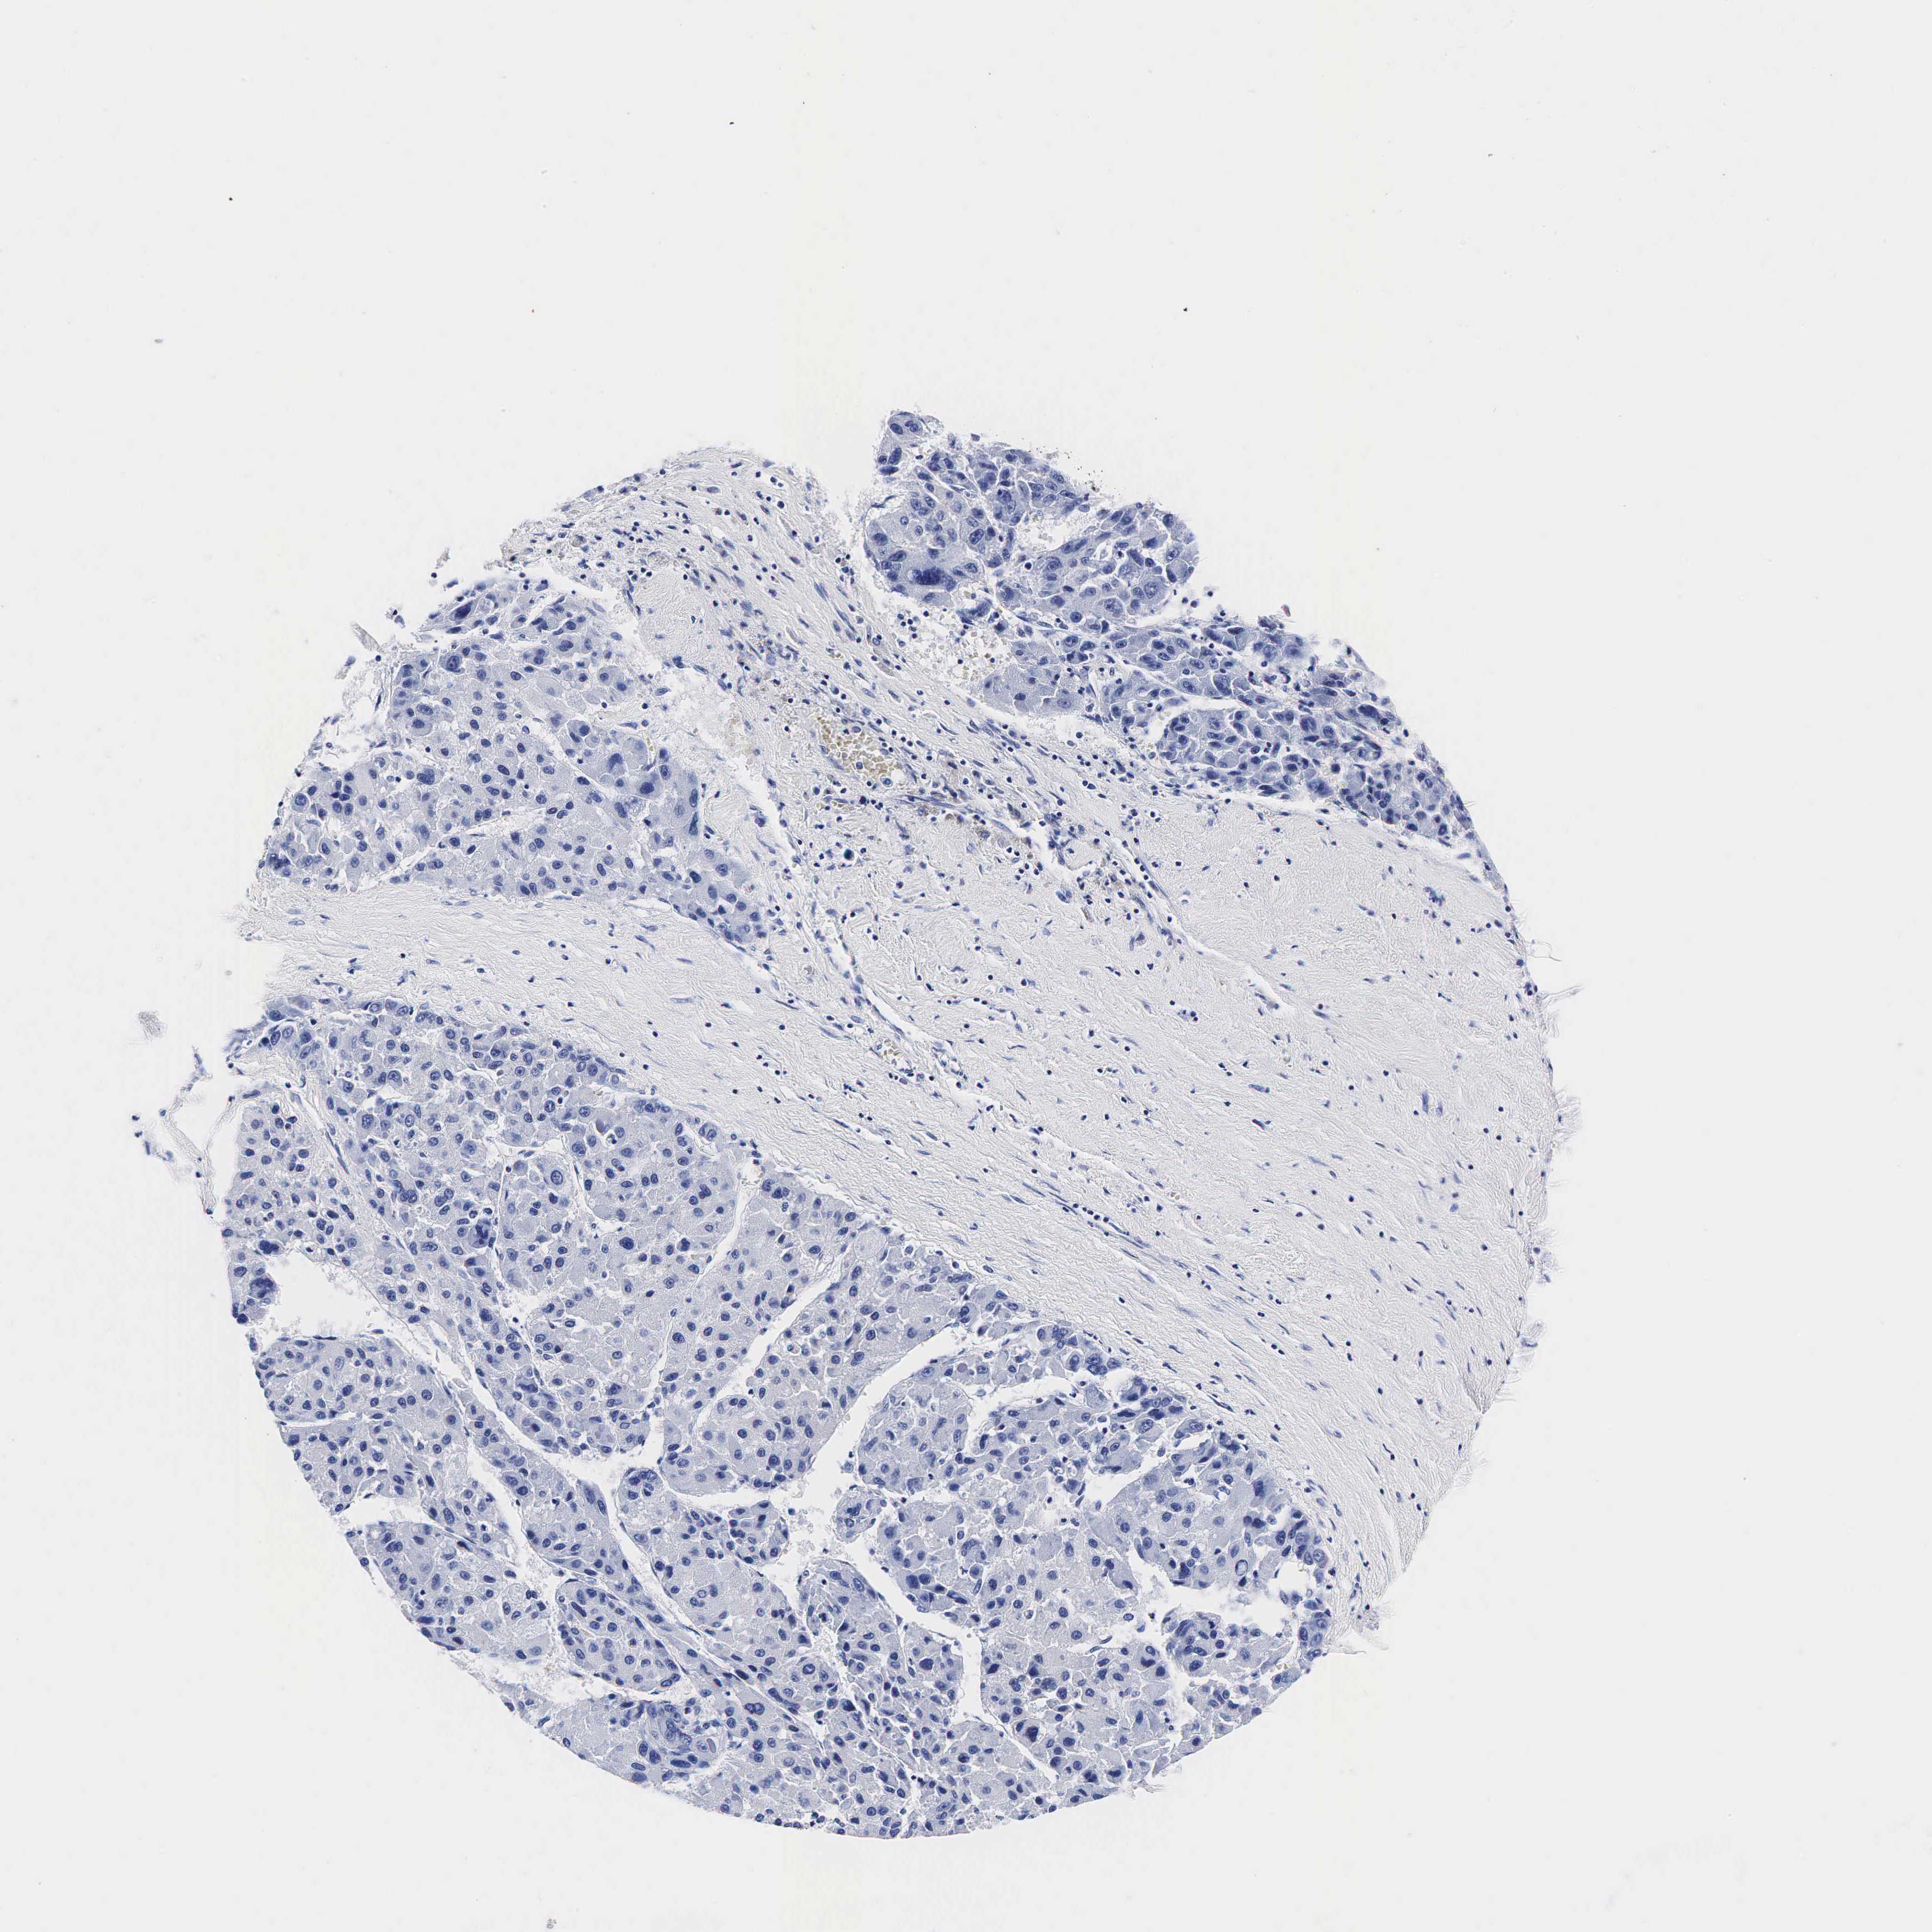

LIVER CANCER - Protein expressioni

A mouse-over function shows sample information and annotation data. Click on an image to view it in a full screen mode. Samples can be filtered based on level of antibody staining by selecting one or several of the following categories: high, medium, low and not detected. The assay and annotation is described here.

Note that samples used for immunohistochemistry by the Human Protein Atlas do not correspond to samples in the TCGA dataset.

Antibody stainingi

Antibody staining in the annotated cell types in the current human tissue is reported as not detected, low, medium, or high, based on conventional immunohistochemistry profiling in selected tissues. This score is based on the combination of the staining intensity and fraction of stained cells.

Each image is clickable and will lead to virtual microscopy that enables deeper exploration of all samples and also displays staining intensity scores, fraction scores and subcellular localization as well as patient and tissue information for each sample.

Antibody HPA002740

Antibody CAB000077

Antibody CAB056155

Staining

High

Medium

Low

Not detected

Intensity

Strong

Moderate

Weak

Negative

Quantity

>75%

75%-25%

<25%

None

Location

Nuclear

Cytoplasmic/membranous

Cytoplasmic/membranous,nuclear

Carcinoma, Hepatocellular, NOS

Cholangiocarcinoma

Carcinoma, metastatic, NOS